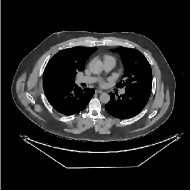

This section compares the reconstruction quality and runtime among the proposed MBIR method, PWLS-ST-, and other three MBIR methods, PWLS-EP, PWLS-DL, and PWLS-ST-. Table I shows that, for both 2D and 3D sparse-view CT reconstructions of the XCAT phantom, the proposed PWLS-ST- model outperforms PWLS-EP and PWLS-ST- in terms of RMSE. In addition, PWLS-ST- using a square transform (of size ) achieves lower RMSE than PWLS-DL using an overcomplete dictionary (of size ) for 2D sparse-view reconstructions. Fig. 3(a) and Fig. 4 show the reconstructed images for 2D and 3D phantom experiments, with different reconstruction models and different number of views. (See the corresponding error maps in the supplement.) The proposed PWLS-ST- consistently gives more accurate image reconstructions compared to other MBIR methods. Specifically, PWLS-ST- has smaller errors in the heart region (see zoom-ins in Fig. 3(a)) of 2D reconstructions than PWLS-DL and PWLS-ST-. In addition, compared to PWLS-ST-, PWLS-DL and PWLS-ST- have some ringing artifacts around the edges with high transition, e.g., edges between air and soft tissues. (See a comparison of profiles of PWLS-ST- and PWLS-ST- in the supplement.) In particular, PWLS-ST- and PWLS-DL give more visible ringing artifacts for 2D reconstruction from fewer views, and PWLS-ST- has these ringing artifacts for 3D reconstructions regardless of the number of views (see zoom-ins in Fig. 4). Table II reports runtimes of different MBIR methods in reconstructing the -views XCAT phantom scan. (FBPConvNet is a non-MBIR method and its runtime for processing a image is approximately one second with a TITAN Xp GPU.) While providing better reconstruction quality, the proposed Algorithm 1 of PWLS-ST- has shorter runtime compared to the algorithms of PWLS-DL and PWLS-ST- in Section III-A. Similar to the PWLS-EP algorithm, the reconstruction time of the PWLS-DL, PWLS-ST-, and PWLS-ST- algorithms can be further reduced by using ordered subsets [51].

![]() |

| (b) 3D axial cone-beam CT experiments |

Fig. S.7 shows the error images (corresponding to Fig. 4) of 3D reconstructed images with the FBP, PWLS-EP, PWLS-ST-, and PWLS-ST- methods. The proposed PWLS-ST- method achieves the lowest RMSE by reducing more noise and reconstructing structural details better, compared to the other methods. In particular, PWLS-ST- has some ringing artifacts around the edges with high transition for both and views (see zoom-ins).